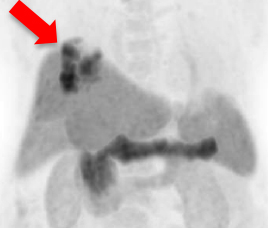

Improvement is seen in most of the lesions on F-18-PSMA PET/CT (indicated by red arrows) after Lu-177 PSMA radionuclide therapy. Lesions become metabolically inactive and less active on post-treatment scan.